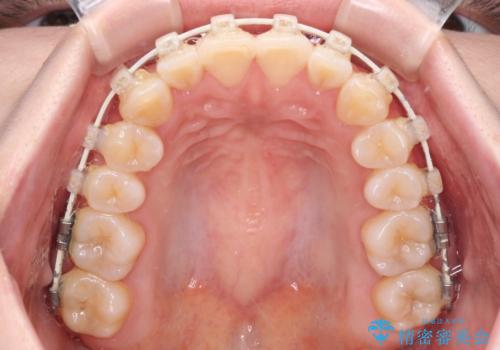

- 矯正装置

- 審美装置

- 上下前歯のデコボコを気にして来院された患者様です。

ワイヤー矯正でもインビザライン矯正でも対応可能でしたが、インビザラインでの自己管理の煩わしさを避けるため、ワイヤー装置にて矯正治療を行うこととしました。

患者様も驚く、僅か10か月での治療終了となりました。

下顎前歯が1歯欠損しているため、上下正中は合わず、左右奥歯の咬み合わせは理想的とはならない仕上がりとなります。